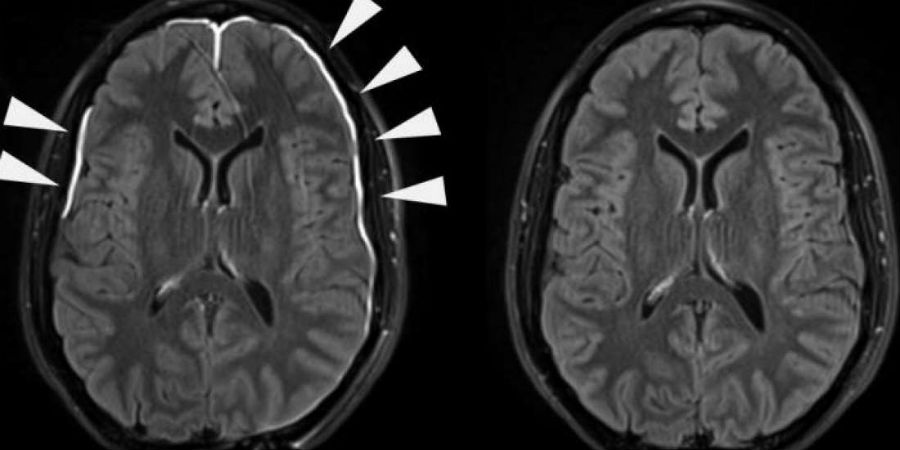

Het onderzoek begon toen artsen MRI-scans van het brein van mensen die nét hersenschade hadden opgelopen, vergeleken met dezelfde scans van vijf weken later. Zoals aangegeven op bovenstaande afbeelding, was er bij de eerste scans lekkage van het vlies te zien (wit), maar bij de meeste mensen was dat na een paar dagen weer verdwenen.